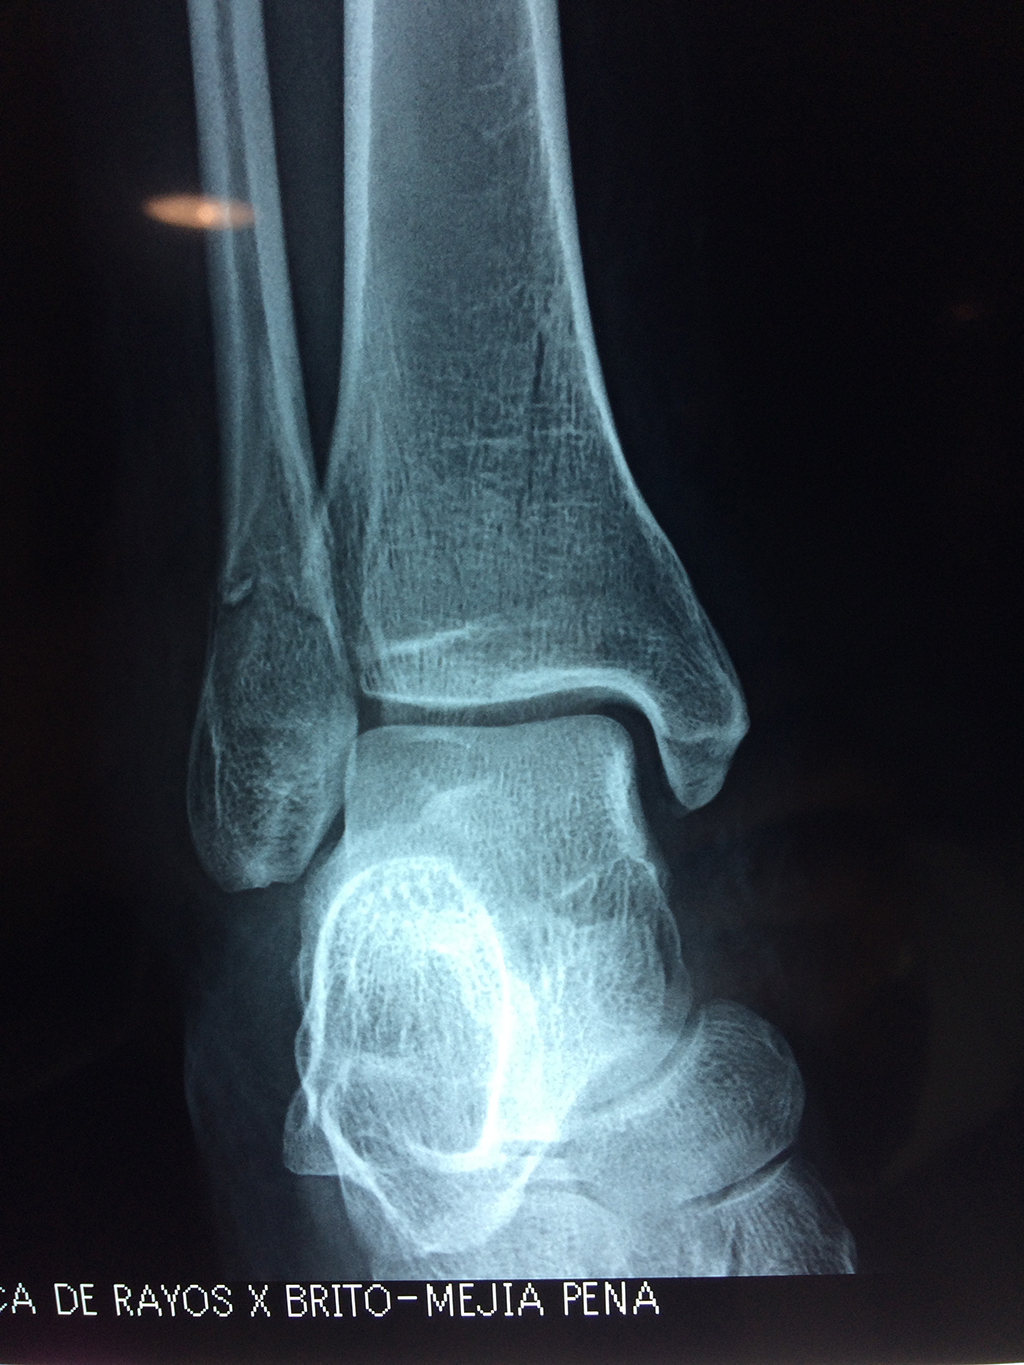

Una fractura de tobillo es la rotura de uno o más de los huesos del tobillo. Estas fracturas pueden ser:

- Parciales (el hueso está sólo parcialmente fisurado, no del todo).

- Completas (el hueso está perforado y está en 2 partes).

- Producirse en uno o ambos lados del tobillo.

Algunas fracturas de tobillo pueden requerir cirugía si:

- Los extremos de los huesos están desalineados entre sí (desplazados).

- La fractura se extiende hasta la articulación del tobillo (fractura intra-articular).

Cuando se necesita cirugía, es probable que esta implique el uso de clavijas de metal, tornillos o placas para sostener los huesos en su lugar mientras la fractura se consolida. Los elementos de soporte pueden ser temporales o permanentes.